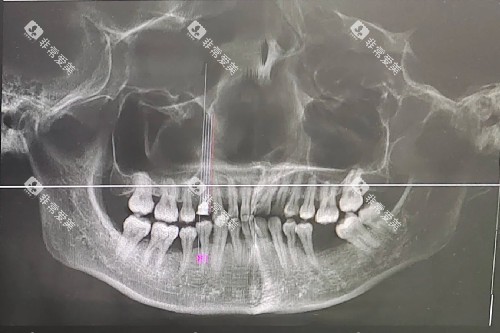

拔牙的收费因牙齿的位置和难度而异。

普通的乳牙拔除和松动牙拔除费用相对较低,一般在几十元到上百元不等。

而智齿拔除由于位置特殊,操作难度较大,收费会相对较高。

智齿拔除的费用可能在几百元到数千元不等,具体取决于智齿的生长情况,如是否阻生、拔除的难易程度等。